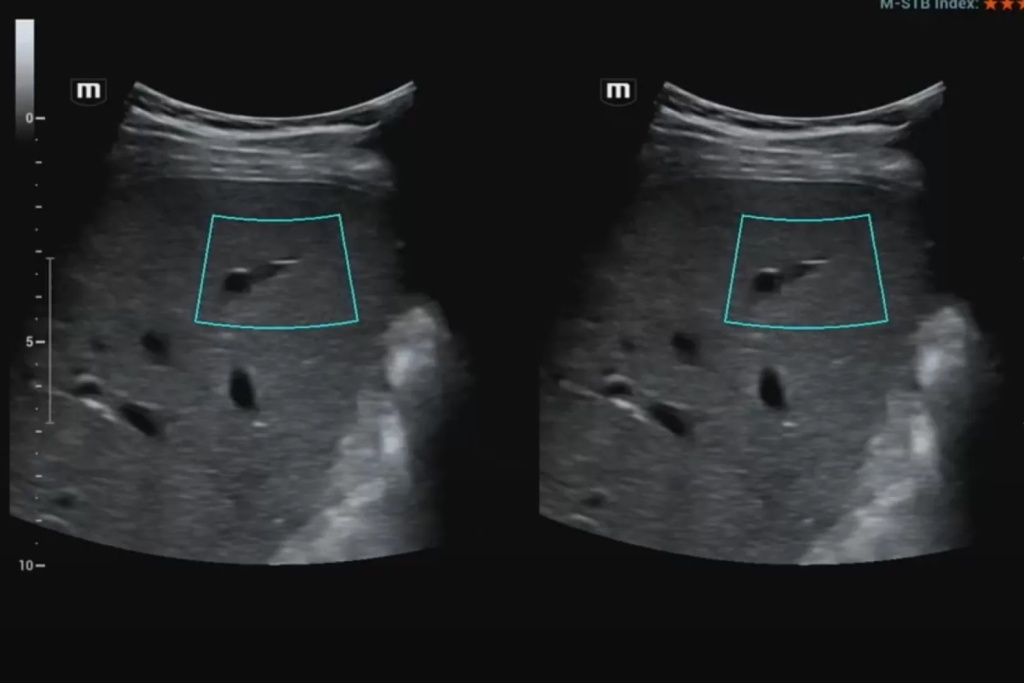

В начале обсудим методику стрейновой эластографии. Она основана на сравнительной оценке деформации (или стрейнов) тканей в области интереса. Деформация может вызываться как приложенной мануальной компрессией, когда мы датчиком слегка надавливаем на подлежащие структуры, так и физиологическими явлениями – передаточной пульсацией сердца, сосудов, дыхательными движениями, а в некоторых случаях и усиленным акустическим импульсом.

В данном случае получение абсолютных значений модуля Юнга (характеризующего жесткость тканей) невозможно, так как его значения зависят от приложенной силы, величина которой не стандартизирована и неизвестна. Поэтому проводится сравнение величины деформации, или стрейна. При воздействии одинаковой силы менее деформируемые ткани являются более жесткими, а более деформируемые – менее жесткими. Ультразвуковой сканер, работающий в специальном режиме, позволяет оценить и сравнить величину деформации тканей в окне опроса и картировать их соответствующим цветом, а также провести полуколичественную оценку – определить отношение деформации в зоне интереса и референсной (условно здоровой) ткани – StrainRatio.

Эластография сдвиговой волной позволяет получить абсолютные значения жесткости исследуемой ткани. В основе данного метода лежит оценка скорости распространения поперечной (боковой) волны, которая может вызываться кратковременным механическим воздействием определенной силы и продолжительности на поверхность тела пациента (это так называемая транзиентная эластография) или сфокусированным усиленным акустическим импульсов в толще исследуемой ткани (именно данные методики в литературе обозначаются как эластография сдвиговой волной). Они в свою очередь подразделяются на методики точечной и двумерной эластографии.